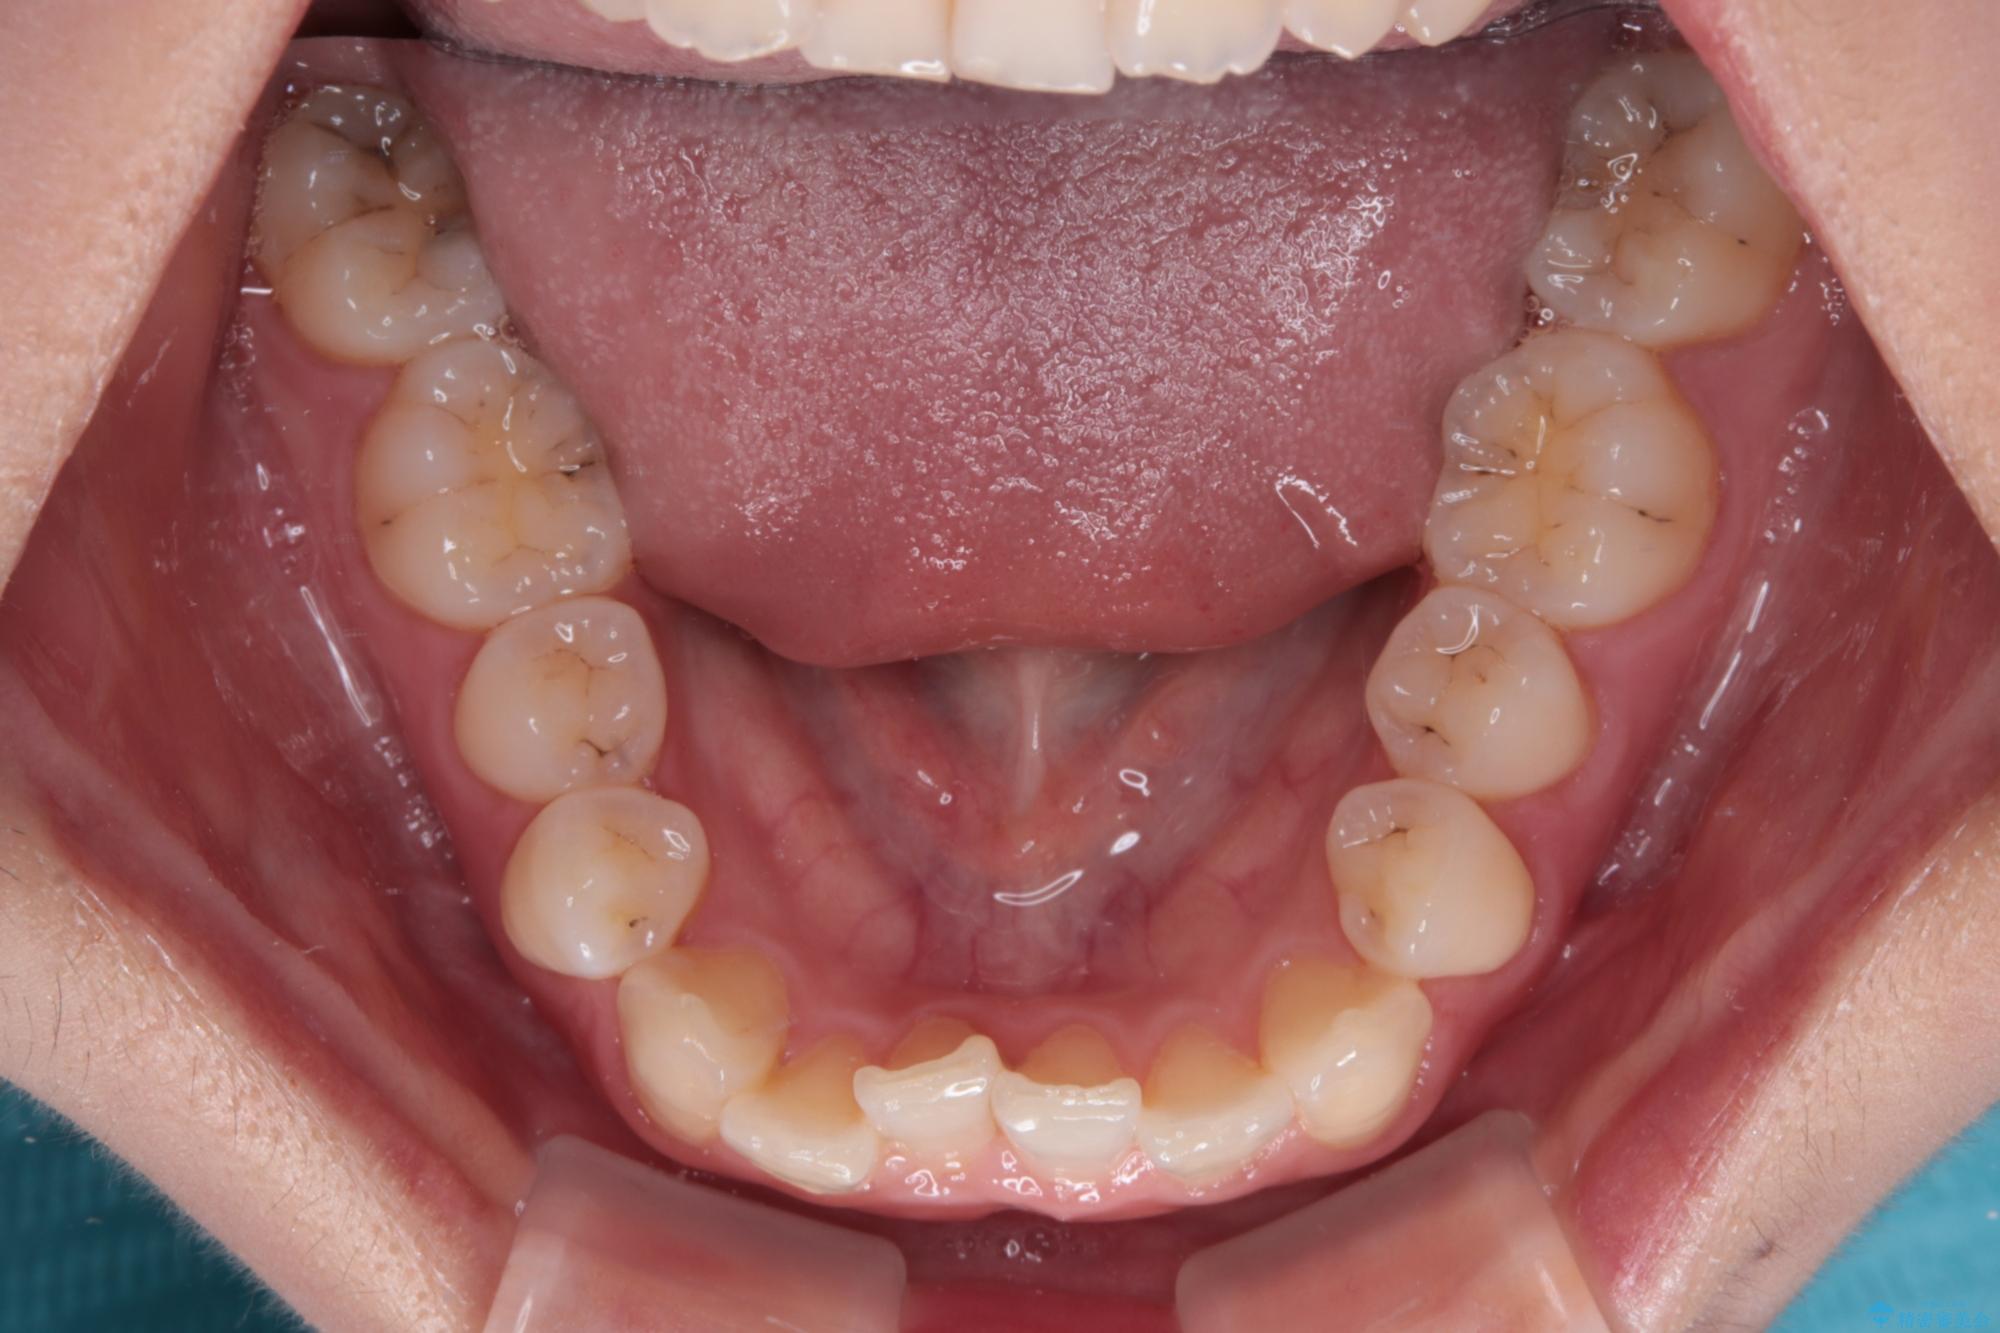

- 上顎前歯のクロスバイトを気にして来院された患者様です。

ワイヤー矯正でもマウスピース矯正でも対応可能でしたが、マウスピースによる自己管理に一切の自信がないとのことで、ワイヤー装置にて矯正治療を行うこととしました。